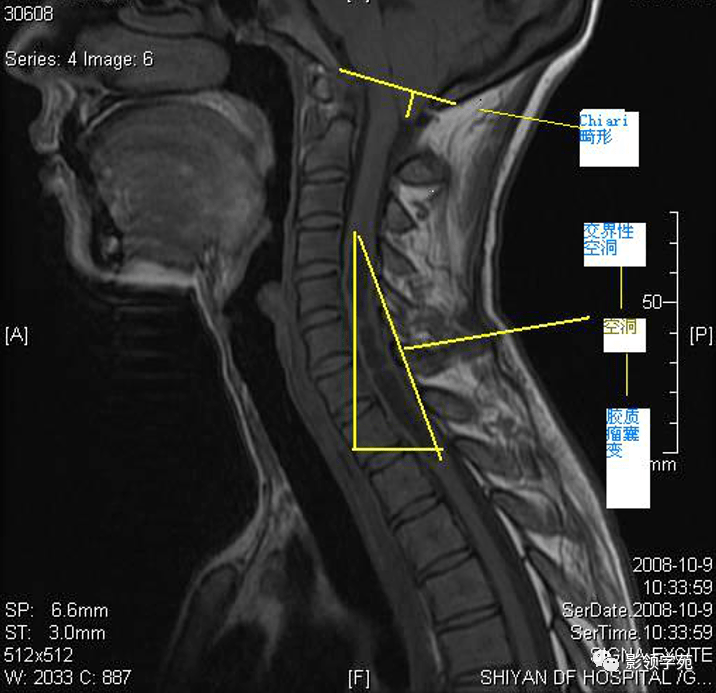

脊髓空洞症影像学表现

脊髓空洞症临床及影像学表现